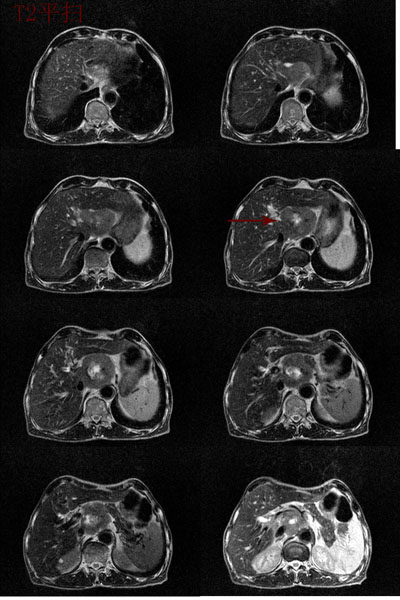

男:62岁:右上腹痛1月。b超报告肝左叶外侧段占位。请讨论灶来源!谢谢!!

腹主动脉前肝左叶后方占位,局部与肝脂肪间隙尚存,故排除左肝来源病变.病灶主体层面位置较高,胰腺受压前移.腹腔干明显拉长包埋.增强后肿瘤边缘性强化.胃小弯侧血管明显增粗.

考虑;后腹膜来源肿瘤.神经源性肿瘤>间叶源性肿瘤>淋巴源性肿瘤.